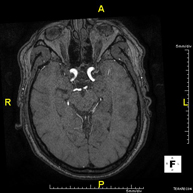

Intracranial MRI angiography

This non-invasive diagnostic procedure uses an electromagnetic field and radio waves (from a transmitter and receiver) to acquire high-definition anatomical images of the cerebral arteries. It is a radiation-free procedure. In most cases, paramagnetic contrast (gadolinium) is required. It enables non-invasive angiographic studies using a gadolinium injection, with subsequent 2D and 3D reconstruction using specialised workstations. Indicated for: Vascular malformations, cerebral artery aneurysms, arteriosclerosis.